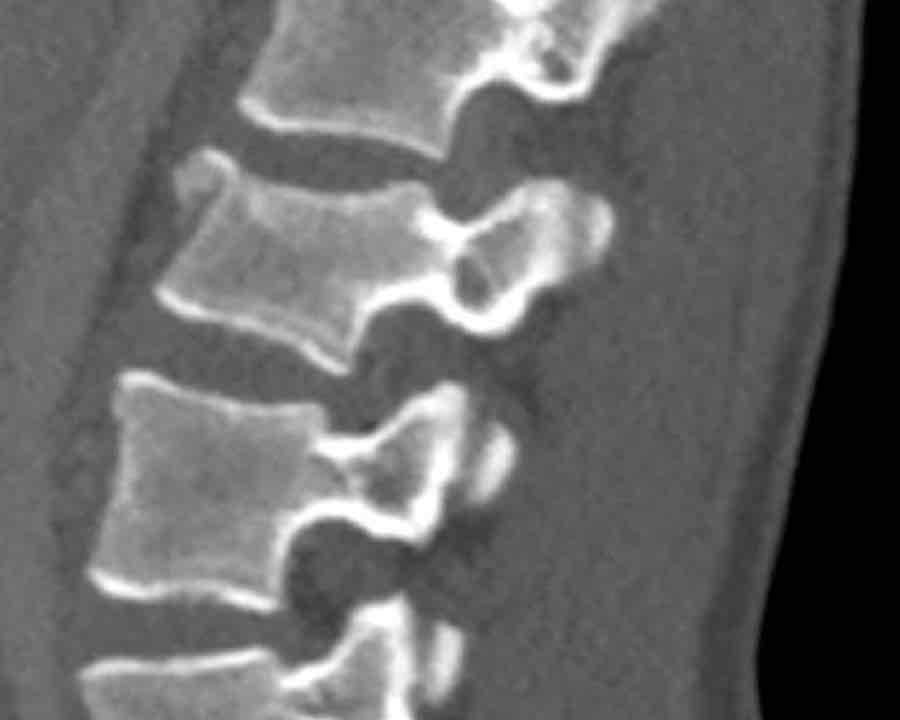

What is the AO-type of the vertebral body fracture based on only these two inages?

Findings:

- Fractures of the vertebral body with involvement of upper endplates (1 points) and posterior wall (2 points)

- Bulging of the posterior wall without any other signs of dislocation is the result of the burst fracture.

Therefore no C injury.

Conclusion

Injury type A3